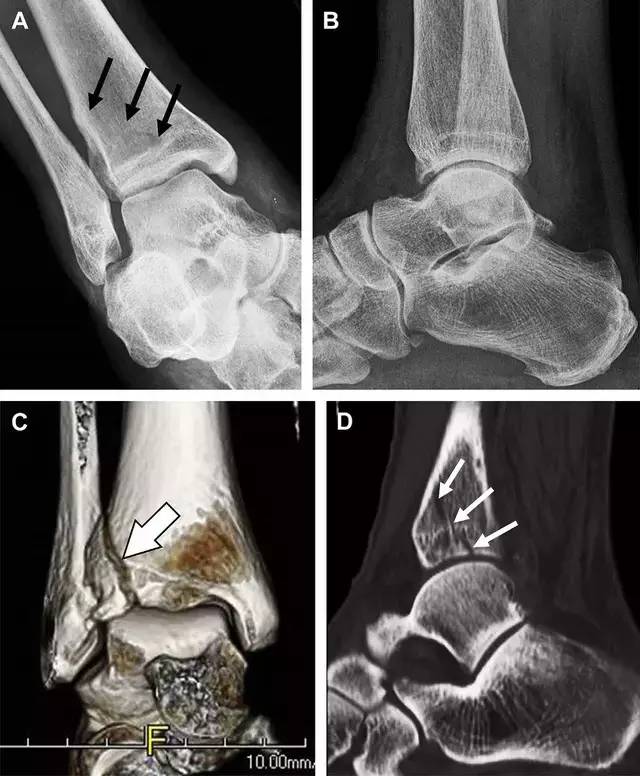

19 距骨后突骨折

距骨后突有内侧结节和外侧结节,距骨后突内侧结节撕脱性骨折常发生在背屈内旋的*力暴**作用下。严重跖屈时,胫骨后缘和跟骨挤压距骨后突外侧结节呈楔形,易发生粉碎性骨折。这些骨折细微且需与三角骨鉴别。侧位片观察距骨后突骨折最佳,常规拍片很难发现,当高度怀疑这种骨折又没法做 CT 时,建议加做多个角度的外旋斜位片(图 5)。

图 5 距骨后突骨折。侧位片(A)和 MRI 矢状位 T1 加权像(B)均示后外侧突的简单骨折(箭头),再次阅片时才发现 X 线片上的骨折;侧位片(C)和 CT 横断面图像示后内侧突的粉碎型骨折(箭头)